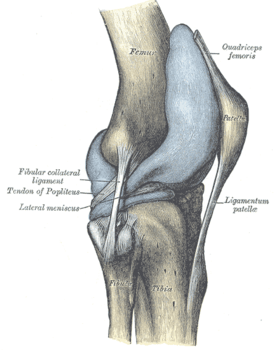

Киста Бейкера – это воспаление синовиальной оболочки капсулы коленного сустава. По своей сути – это воспаление синовиальной оболочки сустава (артрит). При артрите суставная жидкость продуцируется в избыточном количестве. При артрите коленного сустава синтез суставной (синовиальной) жидкости более интенсивный, чем ее всасывание. Жидкость накапливается в суставе, заполняя все карманы капсулы сустава. Когда накапливается много синовиальной жидкости, происходит заполнение в том числе задних карманов капсулы (красные стрелки).

Для лучшего представления о капсуле сустава, внизу приведена иллюстрация из анатомического учебника, которая демонстрирует, насколько сложна объемная капсула сустава и какую она имеет конфигурацию: показаны передний заворот и частично задний.

Каста Бейкера становится видна с момента, когда жидкостью заполняется задний заворот капсулы. В этом случае он легко пальпируется в подколенной ямке (по задней поверхности коленного сустава).

Переполнение синовиальной жидкостью сустава, в частности –задних) заворотов («карманов») —препятствует свободному сгибанию колена, создаёт дискомфорт и чувство переполненности в суставе.